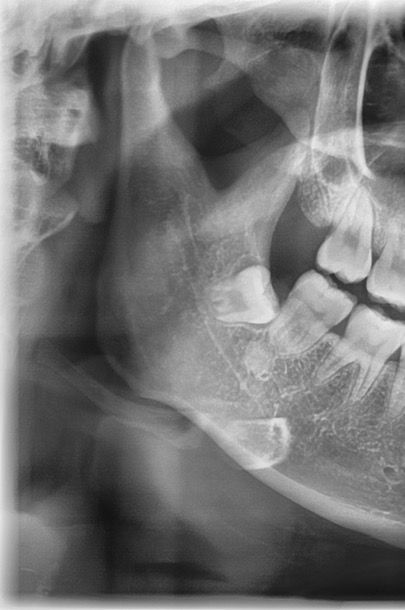

이런 경우 매복 사랑니 꼭 빼야할까요?

이때까지 교정하고 정기검진 10년 가까이 다니면서 사랑니 있다는 말은 따로 못 들어서 사랑니가 없는줄 알았어요

근데 새로운 치과에 치료받으러 갔다가 매복 사랑니가 있어서 아래쪽은 나중에 앞니 뿌리가 상해서 발치를 해야할 수도 있다고 발치 잘하는 병원가서 뽑으라는데 꼭 뽑아야하나요?

이때까지 사랑니가 있는줄도 모를정도로 문제가 없었는데...

• 2번 째 사진

사진에 보이는 사랑니는 특별한 이유가 잇지 않다면 발치를 안하셔도 될것같습니다. 걱정하지 않으셔도 될것같습니다.

사랑니가 완전히 매복되어 있는 경우에는 꼭 발치를 할 필요는 없고 검진만 주기적으로 하셔도 됩니다.

사랑니가 잇몸 안에 완전히 들어가 있다면 굳이 발치를 할 필요가 없습니다. 주기적으로 사랑의 주변에 문제가 발생하지 않는지 치과에서 검진을 받아보는 것이 좋습니다.

옆 어금니를 사랑니가 누르게되면 아주 천천히 뿌리흡수의 가능성도 있긴 합니다 다만 정확히 지금 겹치있는지는 파노라마 사진보고는 판단이 어렵습니다

현재 사랑니가 기울어져서 매복되어 있으며, 이경우 앞의 어금니를 서서히 상하게 합니다. 이를 방치시 나중에 앞의 어금니와 사랑니를 모두 발치해야하는 상황이 오게 되기에 가급적 빠른시일내에 사랑니를 발치하길 권합니다.